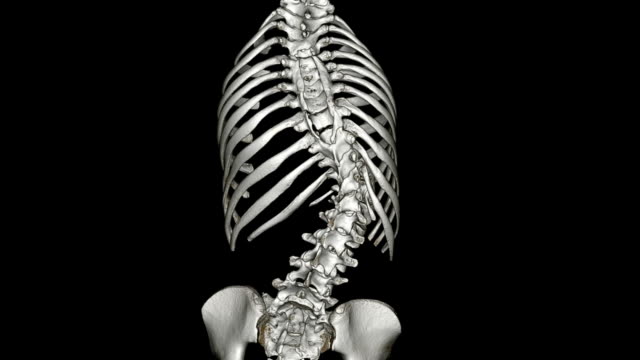

요추 염좌의 원인은 비만, 무리한 운동, 자세 등 다양한 요인과 관련이 있으므로 건강한 생활 습관과 적절한 운동이 필요합니다.

요약하면, 허리 통증과 요추염좌는 일상생활에서 흔히 겪을 수 있는 문제이며, 적절한 치료와 예방을 통해 건강한 척추를 유지하는 것이 중요합니다. 만약 통증이 심하다면 전문의의 도움을 받아보는 것이 좋습니다.